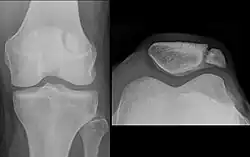

Differentialdiagnosen

Manchmal macht die röntgenologische Abgrenzung der Patellafraktur von einer Patella partita (lat.: zweigeteilte Kniescheibe), also einer während der Entwicklung ausgebliebenen Verschmelzung der Knochenkerne, diagnostische Schwierigkeiten. Während sich frische Frakturen scharfkantig abbilden, findet man bei der Patella partita abgerundete Kanten, die „Fragmente“ sind nicht miteinander kongruent. Auch fehlt bei der Patella partita in der Regel der typische klinische Befund einer Patellafraktur, es besteht keinerlei Funktionsverlust. Wichtig ist die Unterscheidung für die Indikation zur Operation: Nur die frische Fraktur profitiert von der OP.